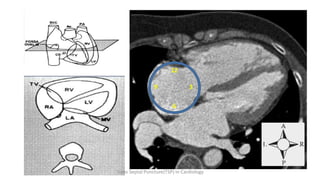

12

9 3

6

Trans Septal Puncture(TSP) in Cardiology

Huge LA with Bulging septum –

Fossa ovalis shifts inferiorly and posteriorly

to 7’ or even 8’ o clock